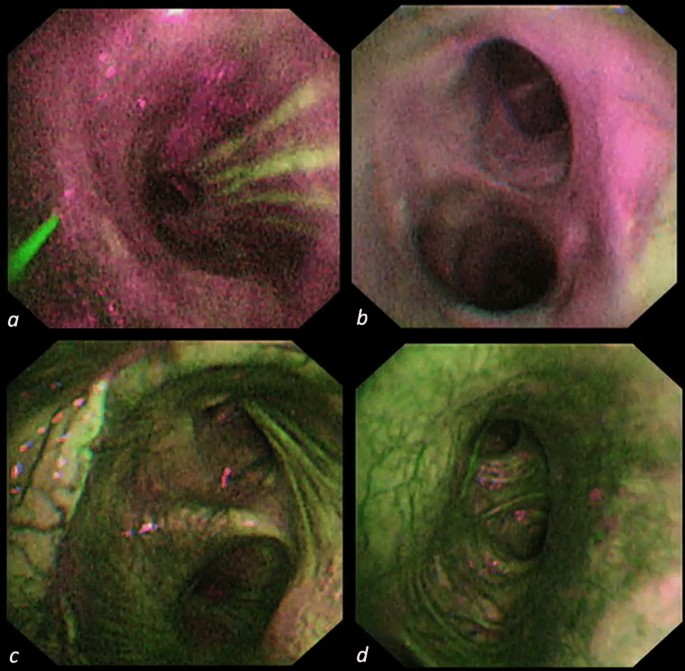

All patients underwent concomitant white-light and AFI bronchoscopy at baseline (immediately after LuTx in the operating theatre after shifting from tracheal double-lumen tube to single-lumen tube), post-operative day POD7, POD14, POD21, POD28, POD45, 3 months, 6 months, and 1 year after LuTx. Anastomoses were classified according to the MDS grading system; for the purpose of the current study, we considered complicated anastomoses as rated higher than M0D0S011. The EVIS LUCERA SPECTRUM endoscopic video imaging system combined with BF-F260 autofluorescence video bronchoscope (Olympus Medical Systems Corp.) was employed to evaluate the conditions of patients’ post-transplant airways12. AFI shows normal vascularized bronchial mucosa as green colored, while the ischemic mucosa as an intense red color13. We obtained an autofluorescence image of the first bronchial carina distally to each anastomosis at sequential time-points. The images were analyzed using histograms for red and green pixels, obtained with a commercial raster graphics editor (Adobe inc., California, U.S.); the R/G ratio was recorded.

The same physician (RC) performed all procedures. Figure 1 shows AFI bronchoscopy at different time-points after LuTx.

Remarkable enhancements in endoscopic technology have been crucial in the improvement of airways evaluation. Fluorescence bronchoscopy, which was developed as a method for detecting early lung cancers and dysplastic lesions of the tracheobronchial tree, can assess the airway in terms of vascular supply of the bronchial mucosa. AFI is a technology that employs the inherent properties of short wavelength blue light to assess mucosal tissues. When the blue excitation light (390–470 nm) reaches the subepithelial layer of healthy tissue, it will appears green as a consequence of the fluorescence emitted from fluorescent substances such as collagen and light of wavelength 540–560 nm, which is absorbed by circulating hemoglobin. If any subtle mucosal change—such as decreased vascularization or thickening of the mucosa—occurs on the surface layer, fluorescence decreases and the tissue appears as magenta13. In light of that, it is legitimate to assume that this technology might help in identifying ischemic bronchi and that, by grading the R/G ratio, it would enable operators to avoid possible anastomotic complications. Not surprisingly, all patients displayed completely red (ischemic) bronchial mucosae at early post-operative checks, although the mucosa appeared pink and completely trophic in white light. By the time the entire study interval passed (12 months), the bronchial mucosa acquired a green tone similar to that of the pre-anastomotic healthy native mucosa. In our cohort, no signs of ischemia, necrosis, or anastomotic dehiscence were detected; conversely, 8 grafts developed post-anastomotic stenosis. It is interesting to note that the “normalization” of the R/G curve diverged significantly from the third postoperative month despite the fact that grafts with post-anastomotic bronchial stenosis had an average complication onset time of 201 days. This evidence opens up the possibility of speculating on the potential predictive capacity of the AFI in terms of development of post-anastomotic bronchial stenoses.